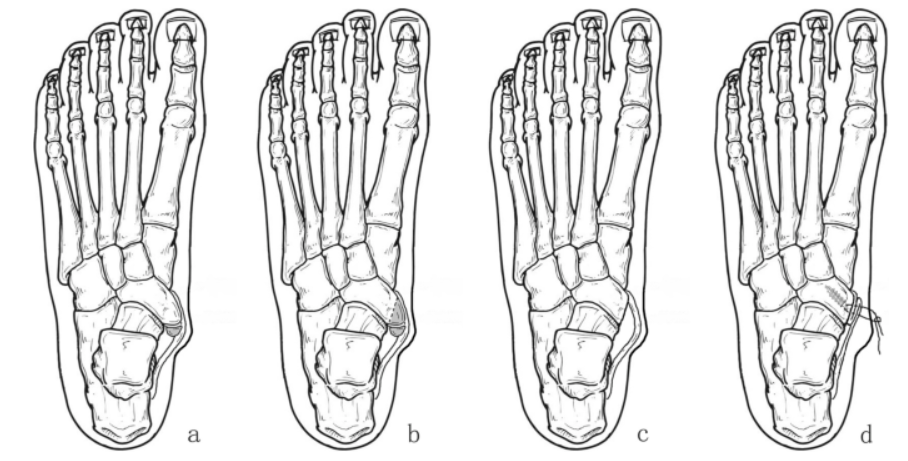

보존적 치료가 우선이며, 휴식, 약물 (소염제) 복용, 발 모양 교정 깔창 착용 등이 시행됩니다.

심하면 부주상골 부위에 깁스나 보조기 착용으로 안정화합니다.

보존 치료로 호전되지 않거나 기능 손상이 심한 경우, 부주상골 제거술이나 후경골건 이전술 같은 수술적 치료를 고려합니다.

평발이 동반된 경우 평발 교정 수술과 같이 시행할 수도 있습니다.